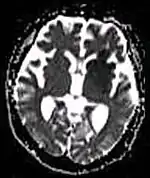

Diffusion weighted (DWI) Conventional DWI Measure of Brownian motion of water molecules.[66] High signal within minutes of cerebral infarction (pictured).[67]

Apparent diffusion coefficient ADC Reduced T2 weighting by taking multiple conventional DWI images with different DWI weighting, and the change corresponds to diffusion.[68] Low signal minutes after cerebral infarction (pictured).[69]